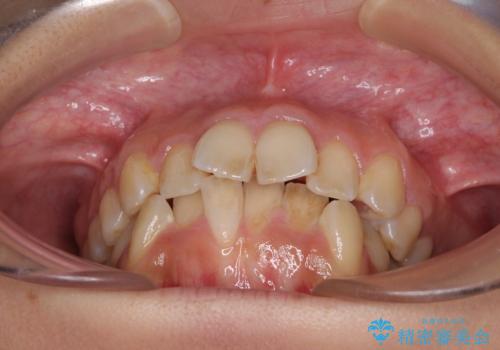

デコボコと口元の突出感 ハーフリンガルでの抜歯矯正

- 前歯のデコボコと上顎の前突感による口の閉じにくさを気にして来院された患者様です。

目立たない装置を希望されたので、上顎が裏側装置のハーフリンガルを選択し、上下左右の小臼歯(計4歯)を抜歯して矯正治療を行うこととしました。